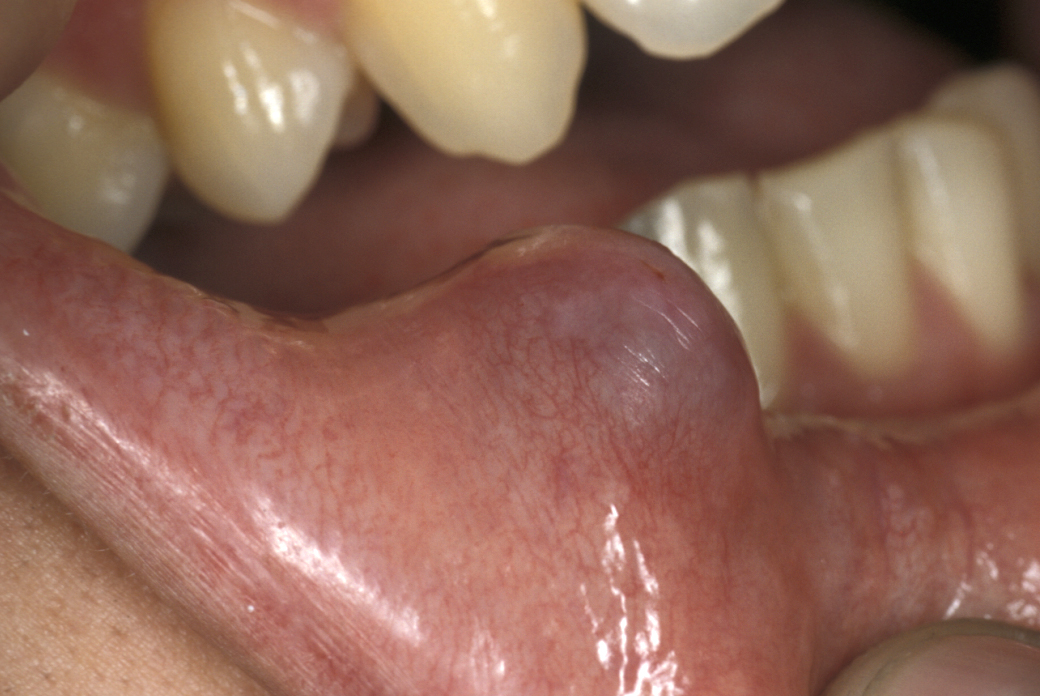

Eruption cysts - these cysts are soft tissue analogues of dentigerous cysts and usually overlie unerupted teeth. They tend to affect children and involve deciduous teeth (milk teeth). They appear as a soft, translucent, bluish swelling (see Figure 3).